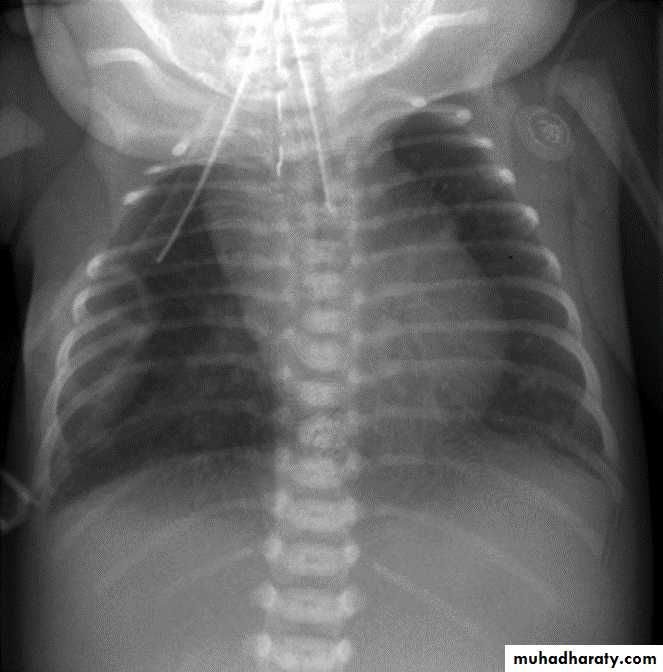

ATRESIA:

1-Complete blockage of the lumen .

2- The diagnosis is suggested after birth by inability of infant to feed or by choking during swallowing .

3- The blocked segment is mostly seen at level of thoracic inlet

TYPES OF FISTULA